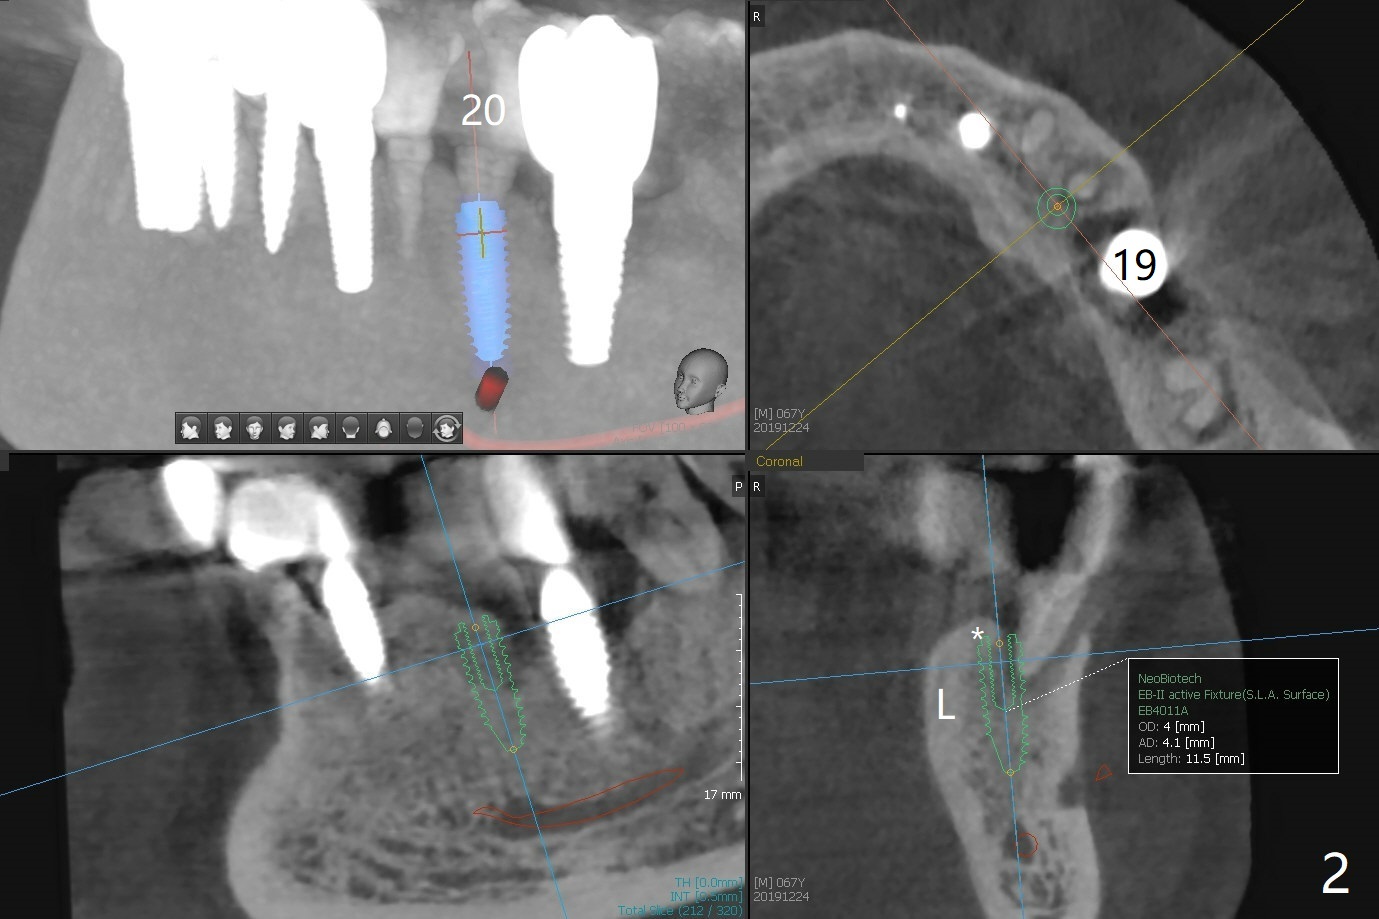

A 67-year-old man with history of chronic periodontitis and bruxism returns to clinic requesting implant for the tooth #20 with mobility (Fig.1). To assure No Deviation of implant placement, Lindamann bur will be used to remove the most coronal of the buccal aspect (Fig.2 *, 3 pink dashed line) of the thick lingual plate (L) during osteotomy. To reduce bone loss (Fig.4 *) associated with residual cement (Fig.4,5 arrowheads) of the tissue-level implants, a bone-level one (SM) will be used at #20. Check whether the nearby implant (#19) has infection clinically and bone graft if needed. Buccolingual threads of the #27 implant are also exposed 3 years 9 months post cementation (Fig.6). An ideal treatment is probably to remove the 4.5x17 mm tissue-level implant and place a 3.8x10 mm bone-level one deeper and a little mesial with bone graft.